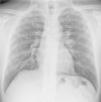

Case 2A 50-year-old man, non-smoker, who since 1981 has worked in the same company as Case 1, performing similar tasks. Since 2000, he has intensively used artificial quartz conglomerates for constructing kitchen and bathroom surfaces. The patient was asymptomatic and lung function test results were normal. Chest X-ray was performed twice, in 2011 (during routine medical examinations ordered by the company) and in 2013 (Fig. 1). In 2011, ILO classification showed nodular q-p opacities with 2/2 profusion in both lungs, mainly in the upper and middle lung zones. In 2011, lung HRCT according to ICOERD classification showed prevalent well-defined rounded grade 2 opacities, predominantly size q, profusion grade10 (Fig. 2). The patient was assigned to different tasks in order to prevent further exposure, but in 2013 the radiographic abnormalities according to ILO classification had increased (q/r opacities with profusion 2/3 in both lungs and large type A opacities). ANA and anti-ENA levels were normal. QuantiFERON testing for Mycobacterium tuberculosis was negative. Mycobacteria detection with direct microscopy, culture and PCR, and bacterial and mycological culture of BALF were all negative. Cell count showed lymphocytosis (41%) and a decreased CD4+/CD8+ratio.